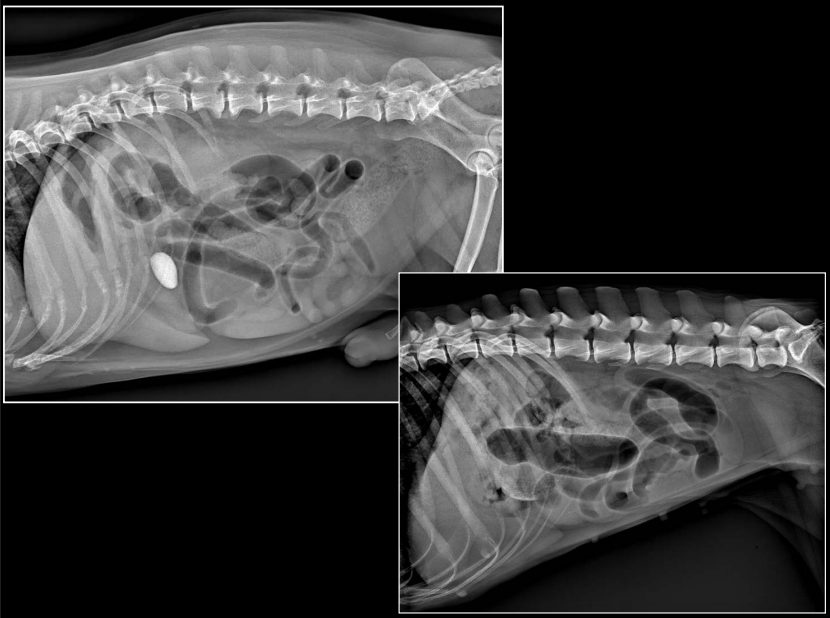

INTESTINO DELGADO

(Imagen: perro y gato comparativos.)

RX:

- Dos poblaciones de asas (normales / dilatadas)

- Diámetro aumentado

- Asas distendidas, paralelas

OBSTRUCCIÓN MECÁNICA

(Cuerpo extraño / invaginación / masas)

Importante saber a que diametro se considera que las asas han incrementado.

PERRO: diámetro normal I.D / L5 < 1,4

GATO: diámetro normal I.D / L2 < 2